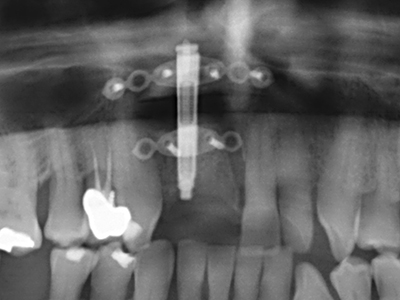

Wie sich in der Vergangenheit gezeigt hat stellt prinzipiell jeder knochenchirurgische Eingriff eine mögliche Indikation für die Piezochirurgie dar. So lässt sich die Präparation des mobilen Segmentes bei der Distraktionsosteogenese (Abb. 23-25) und der Sandwichosteotomie mit speziellen Ansätzen bewerkstelligen, ohne die für den Erfolg beider Techniken essenzielle Blutversorgung des krestalen Anteils zu gefährden (Gonzalez-Garcia, Diniz-Freitas et al. 2008).

Weitere Einsatzgebiete ergeben sich in der Kieferhöhlenchirurgie: Hier können nach konzentrischer Präparation eines in der Regel trapezförmigen Knochendeckels der fazialen Kieferhöhlenwand Pathologien und Fremdkörper aus der Kieferhöhle entfernt werden. Der Knochendeckel wird nach Abschluss des intra-antralen Operationsanteils reponiert und durch Verkeilen oder adaptierende Nähte gegen Dislokation gesichert.